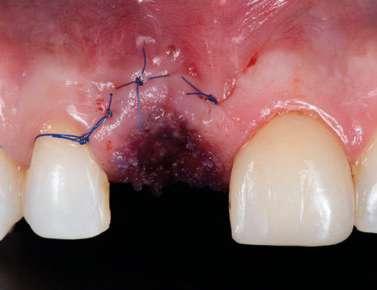

El diente 11 fue extraído (Figura 4), seguido por la preservación alveolar. Se realizó un injerto pediculado de espesor parcial rotado del paladar (Figura 5), junto con una membrana de colágeno reabsorbible, un xeno-injerto bovino y cianoacrilato sellando al alveolo (Figura 6). La provisionalización consistió en un puente adhesivo de resina con dos alas de metal. El alveolo se dejó cicatrizar durante 6 meses, después de los cuales se tomó una impresión digital así como un escáner CBCT (Figura 7). Se llevó

a cabo una planificación digital para una cirugía guiada de implante en una posición protéticamente ideal (Figura 8). El implante 11 se colocó completamente guiado a través de una férula (Figura 9). Las dimensiones del reborde alveolar eran ideales para la colocación del implante en una posición atornillada (Figura 10), al igual que la calidad del hueso cicatrizado. Un injerto de tejido conectivo subepitelial fue estabilizado ocluso-bucalmente al implante (Figura 11) y el puente adhesivo fue recementado (Figura 12). Después de 3 meses de cicatrización, se realizó una restauración provisional y se acondicionó adecuadamente para dar forma al perfil de emergencia, imitando el del diente adyacente (Figura 13). Después de una fase provisional, se tomó una impresión analógica individualizada para el implante 11 y el diente 21 (Figura 14). El laboratorio fabricó una corona implantosoportada de zirconio con cerámica estratificada para el 11 y una carilla laminada feldespática para el diente 21 (Figura 15). Ambas restauraciones fueron colocadas en la paciente y mantenidas. La paciente quedó muy satisfecha con el resultado estético de las restauraciones (Figuras 16, 17). Después de 2 años, el implante permanece saludable con el hueso marginal estable (Figura 18) y una buena calidad y cantidad de tejido blando.